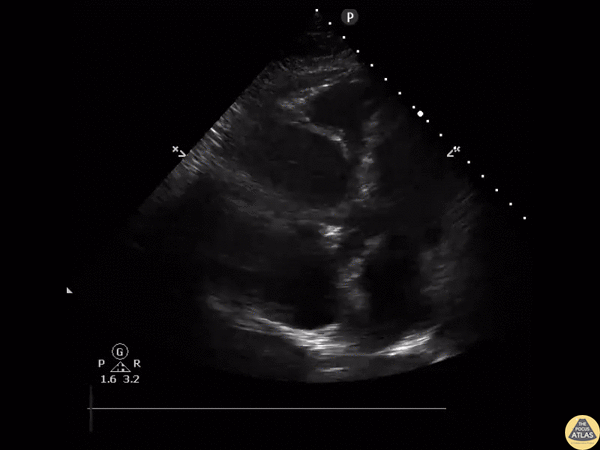

Right Ventricular Dysfunction - McConnell's Sign

A female in her mid-30’s presented to the ED with chest pain and shortness of breath. POCUS at the apical window revealed right ventricular free wall akinesis with sparing of the apex, indicative of McConnell’s sign of a pulmonary embolism. A clot can also be seen within the right atrium. Image courtesy of Robert Jones DO, FACEP @RJonesSonoEM Director, Emergency Ultrasound; MetroHealth Medical Center; Professor, Case Western Reserve Medical School, Cleveland, OH View his original post here